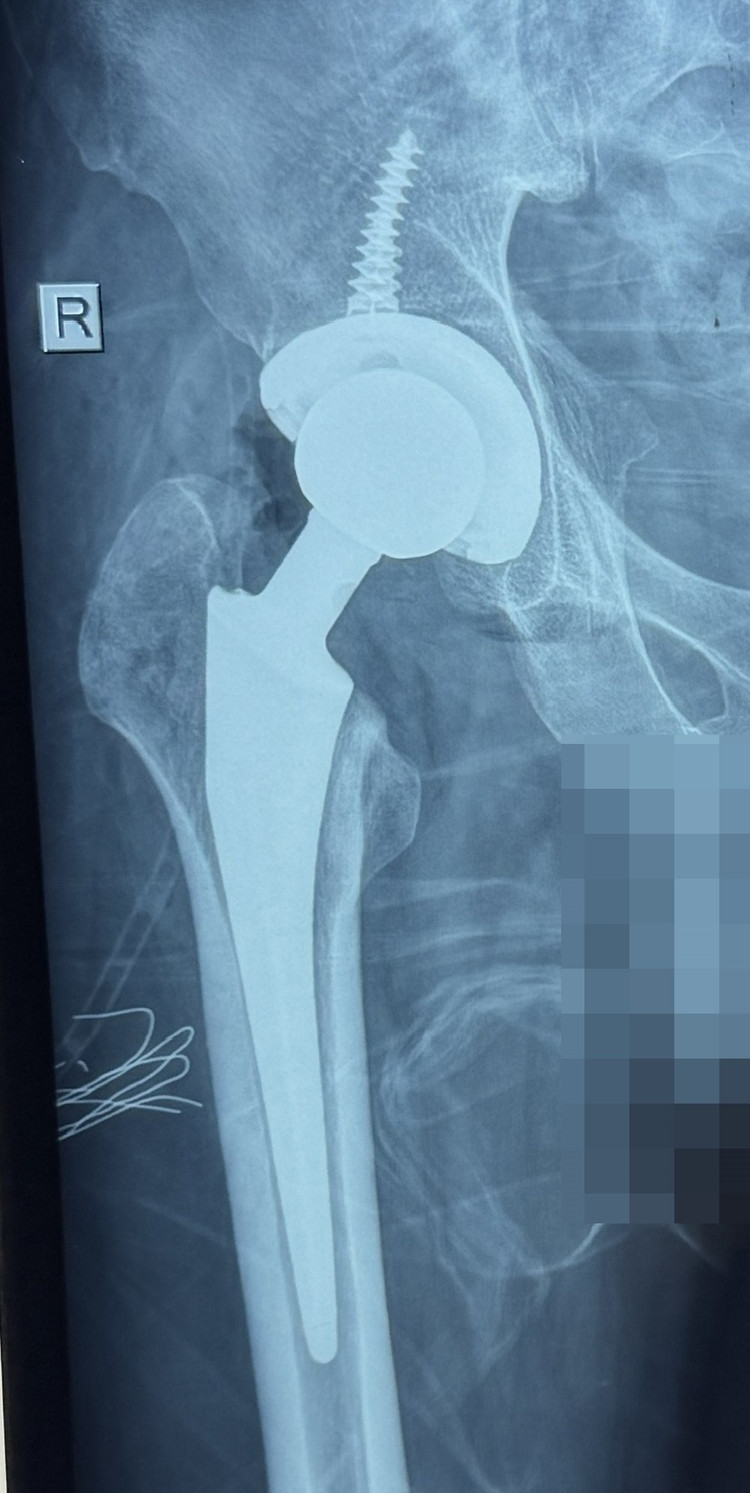

Bệnh nhân đến khám tại Bệnh viện Đa khoa Xuyên Á Vĩnh Long, kết quả chụp X-quang cho thấy rõ hình ảnh hoại tử chỏm xương đùi phải. Người bệnh được các bác sĩ tư vấn cụ thể về tình trạng sức khỏe và phương án phẫu thuật tối ưu nhất là thay khớp háng toàn phần qua lối trên trực tiếp.

Thay khớp háng do hoại tử vô khuẩn chỏm xương đùi trên phim chụp - Ảnh BVCC

Ca phẫu thuật được thực hiện dưới sự dẫn dắt của BS.CKI. Phạm Văn Thắng – Phó khoa. Cuộc phẫu thuật được thực hiện trong 2 giờ. Sau phẫu thuật bệnh nhân đã giảm đau nhiều, có thể đi lại được vài ngày sau mổ.